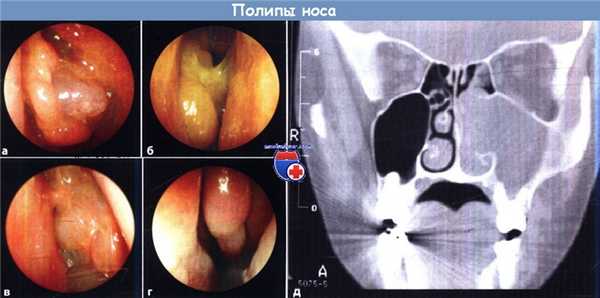

Различные типы полипов носа (а-г: осмотр эндоскопом с торцевой оптикой)

а Хронический гиперпластический (неопухолевый) риносинусит.

б Клиническая триада: непереносимость аспирина, бронхиальная астма и полипоз носа: типичный цвет слизистой оболочки, изменение реологических свойств слизистого слоя и его утолщение.

в Индурация и развитие рубцов после повторного удаления полипов.

г, д Антрохоанальный полип; это единственный полип, который исходит из верхнечелюстной пазухи.